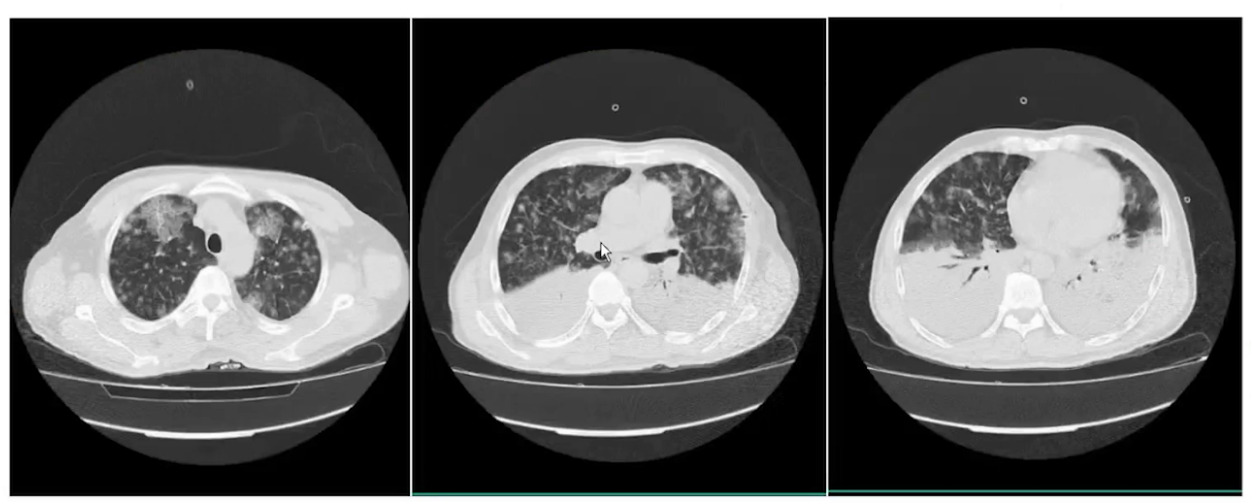

入院后予以Highflow改善氧合,间断俯卧位通气。先后予以美罗培南针1.0静滴q12h(11.08-11.26),头孢他啶针2.0静滴bid(12.01-12.18)、莫西沙星针0.4静滴qd(12.03-12.18)抗感染。甲泼尼龙针抗炎,静注人免疫球蛋白 (pH4)20g(1.10-11.13)调剂免疫治疗。那屈肝素钙抗凝、抑酸护胃等对症治疗。期间患者Highflow参数渐进性上调,氧合渐进性持续恶化,病情渐进性加重。

(3)随访影像学变化